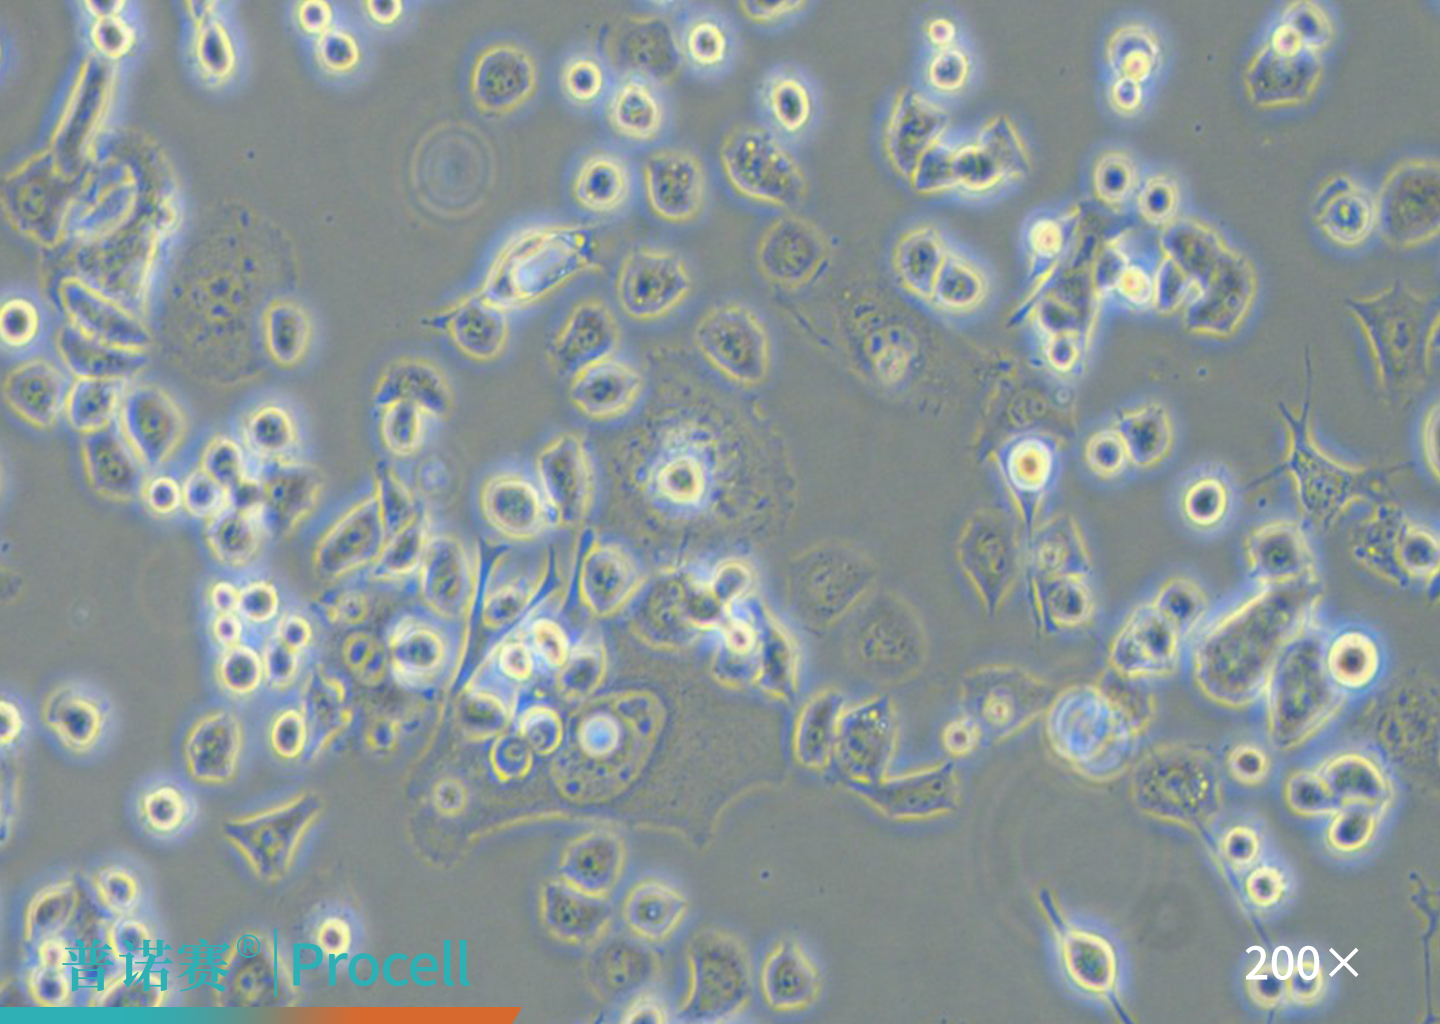

一、SH-SY5Y(人神经母细胞瘤细胞)

SH-SY5Y细胞的显微镜观察图 SH-SY5Y细胞的显微镜观察图

图1. SH-SY5Y细胞的显微镜观察图